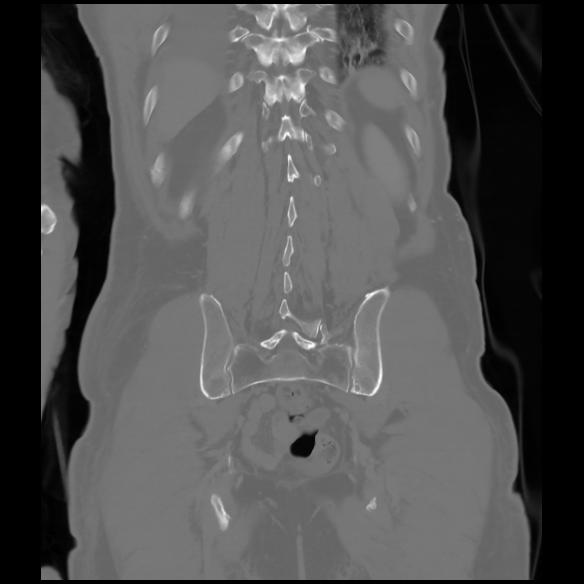

6 CUERPO,CE,Coronal,3.000,CUERPO,Coronal,